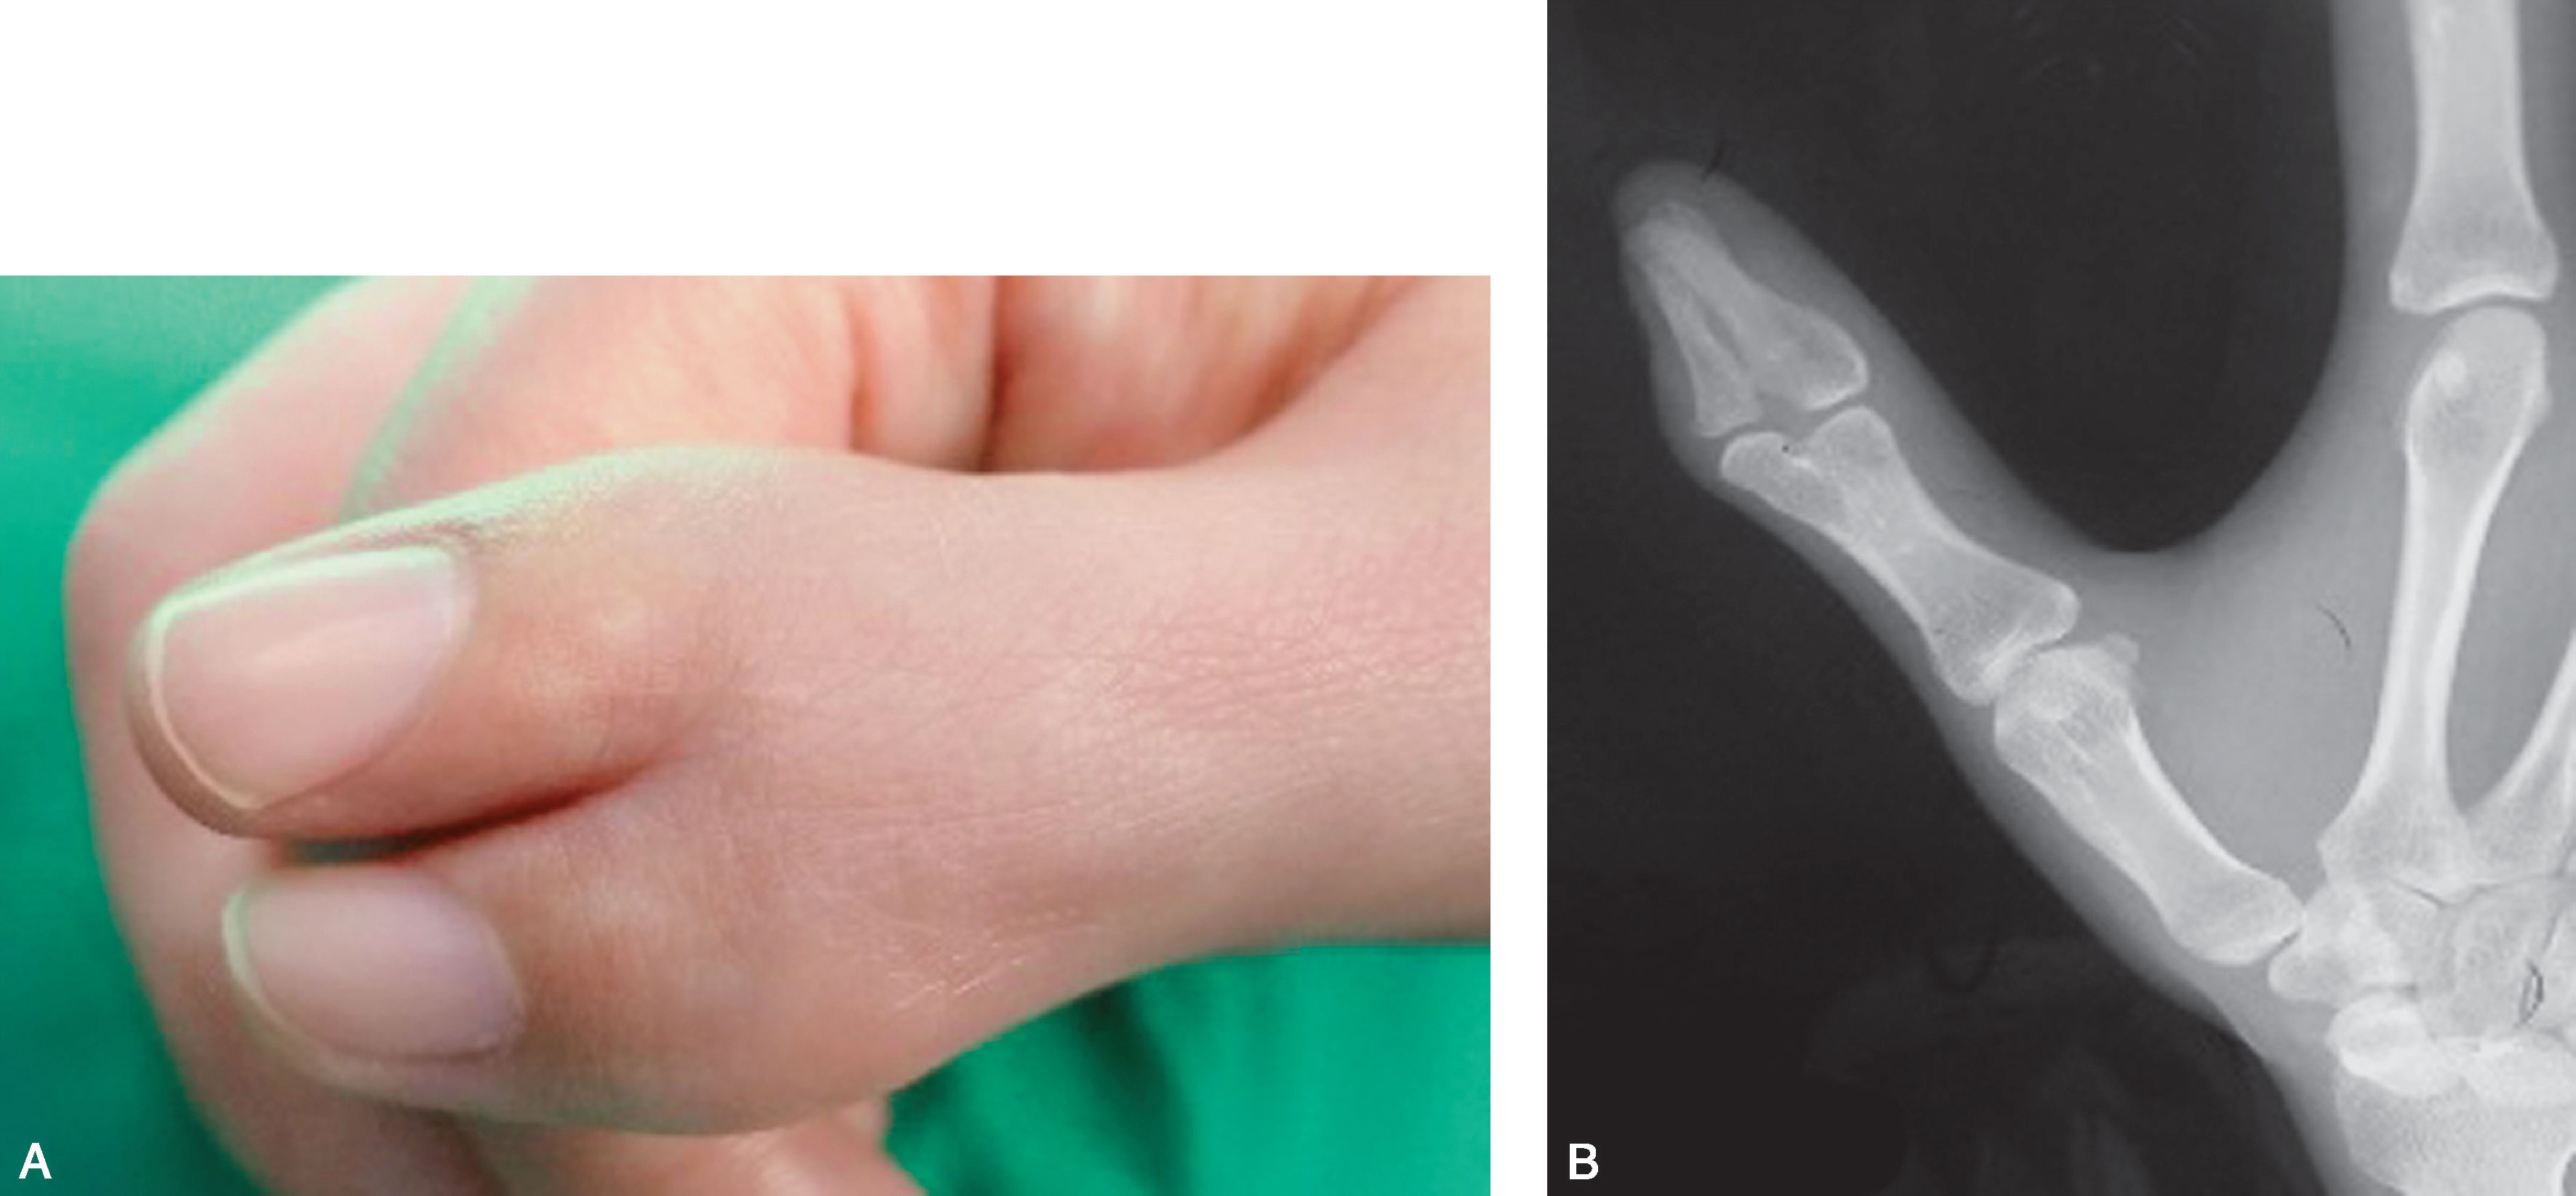

图2-1-46 Ⅶ型病例1

A.右侧多拇指,桡侧拇指发育明显差;B.X 线片显示桡侧拇指为三节细小的指骨,尺侧拇指骨关节结构发育良好,应选择切除桡侧拇指,切除桡侧拇指后,除重建拇短展肌外,尚需行第一掌骨远端桡侧楔形闭合截骨,纠正掌骨力线